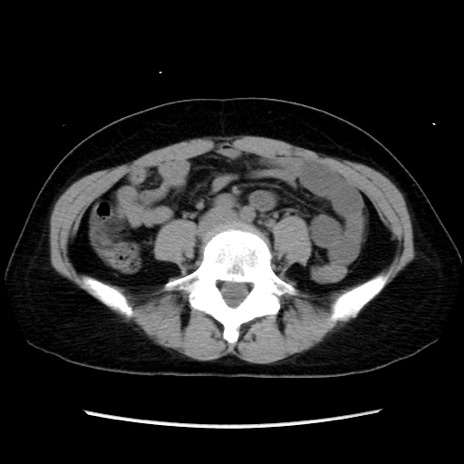

矢状断像

【症例】 50歳代女性

【主訴】 腹痛

【現病歴】前日生レバーを食べた。今朝に排便あり。 昼前に突然発症の腹痛を生じ、当院救急外来を受診した。

【既往歴】 子宮筋腫にてで子宮全摘後

【身体所見】 意識清明、腹部:平坦、軟、下腹部やや左を中心に圧痛・反跳痛あり、筋性防御あり

【データ】WBC 7800、CRP 0.07